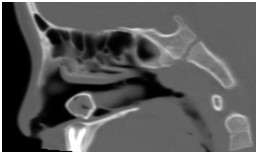

鼻窦(病例-异物):